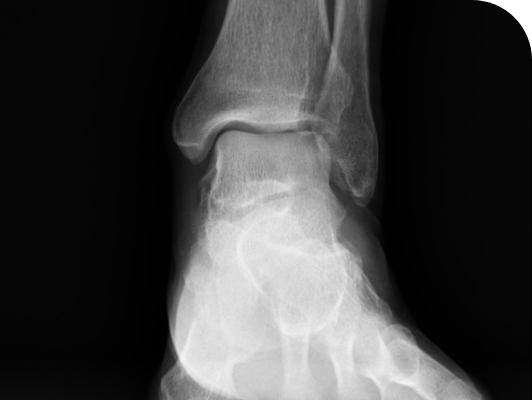

발목의 관절 연골이 닳아 없어지거나 손상되어 정상적인 기능을 하지 못할 때 관절을 인공관절로 대체하는 수술법입니다. 발목 관절 보존 수술을 하기 어려운 말기 발목 관절염에서 시행하는 수술입니다. 발목관절 유합술과는 달리 인공관절을 삽입하여 발목관절의 움직임을 보존하여 원래 걸음걸이를 유지시켜준다는데 장점이 있습니다.

수술 전

발목의 전체부위가 연골이 다 닳아있는 발

수술 후

인공관절이 안정적으로 삽입된 발